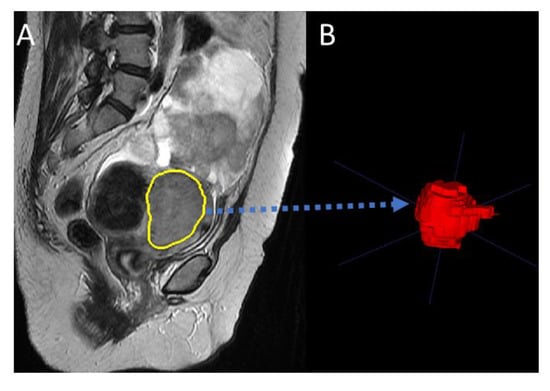

2.2. Data Analysis Pipeline